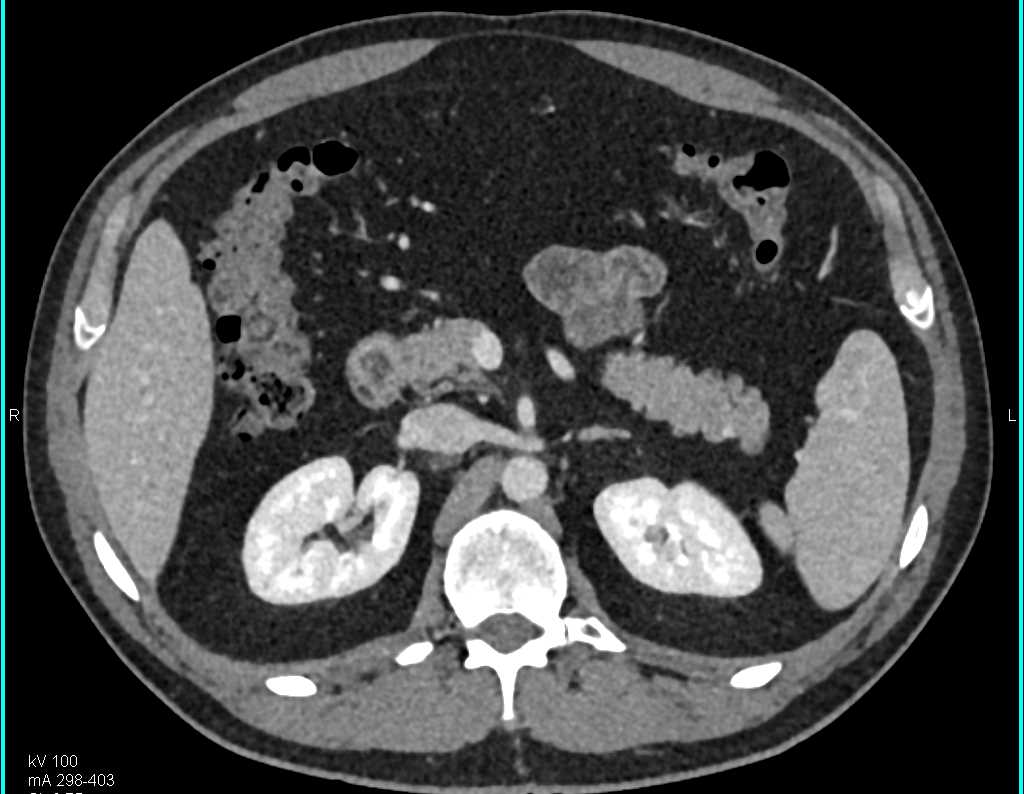

Neuroendocrine Tumor Body of Pancreas